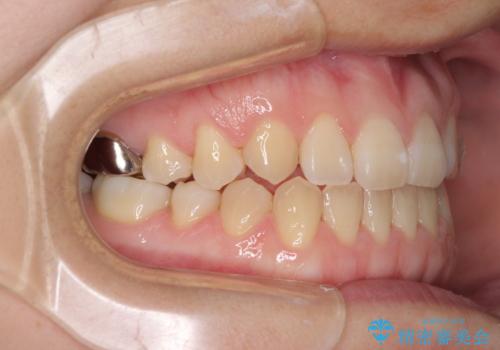

受け口で開咬を急速拡大装置とインビザラインで改善 欠損部分はインプラントにて補綴治療

- 前歯の開咬と、受け口による咬み合わせの悪さを気にして来院された患者様です。

左上は後続永久歯の欠損によりスペースがあり、矯正治療と並行してインプラントあるいはブリッジによる補綴治療が必要な状況でした。

上顎歯列が狭窄していたため、急速拡大装置により上顎骨を側方に拡大し、その後インビザラインにて矯正治療を行うこととしました。

矯正治療と並行してインプラントによる補綴治療を行うこととしました。